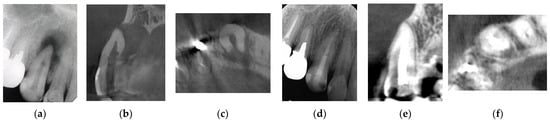

Figure 2. Clinical case 1. Male, age 43 yrs. (a) Preoperative periapical radiograph of the right maxillary canine, with the “bone” defect presenting as a radiolucent area in both the middle of the root and the apical lesion. (b,c) Preoperative CBCT showing a radiolucent lesion on the periapical and palatal areas. This patient underwent endodontic treatment with MTA under microscopy. (d) Follow-up periapical radiograph 4 years later. (e,f) Follow-up CBCT 4 years later, showing filling of the root canal and healing.